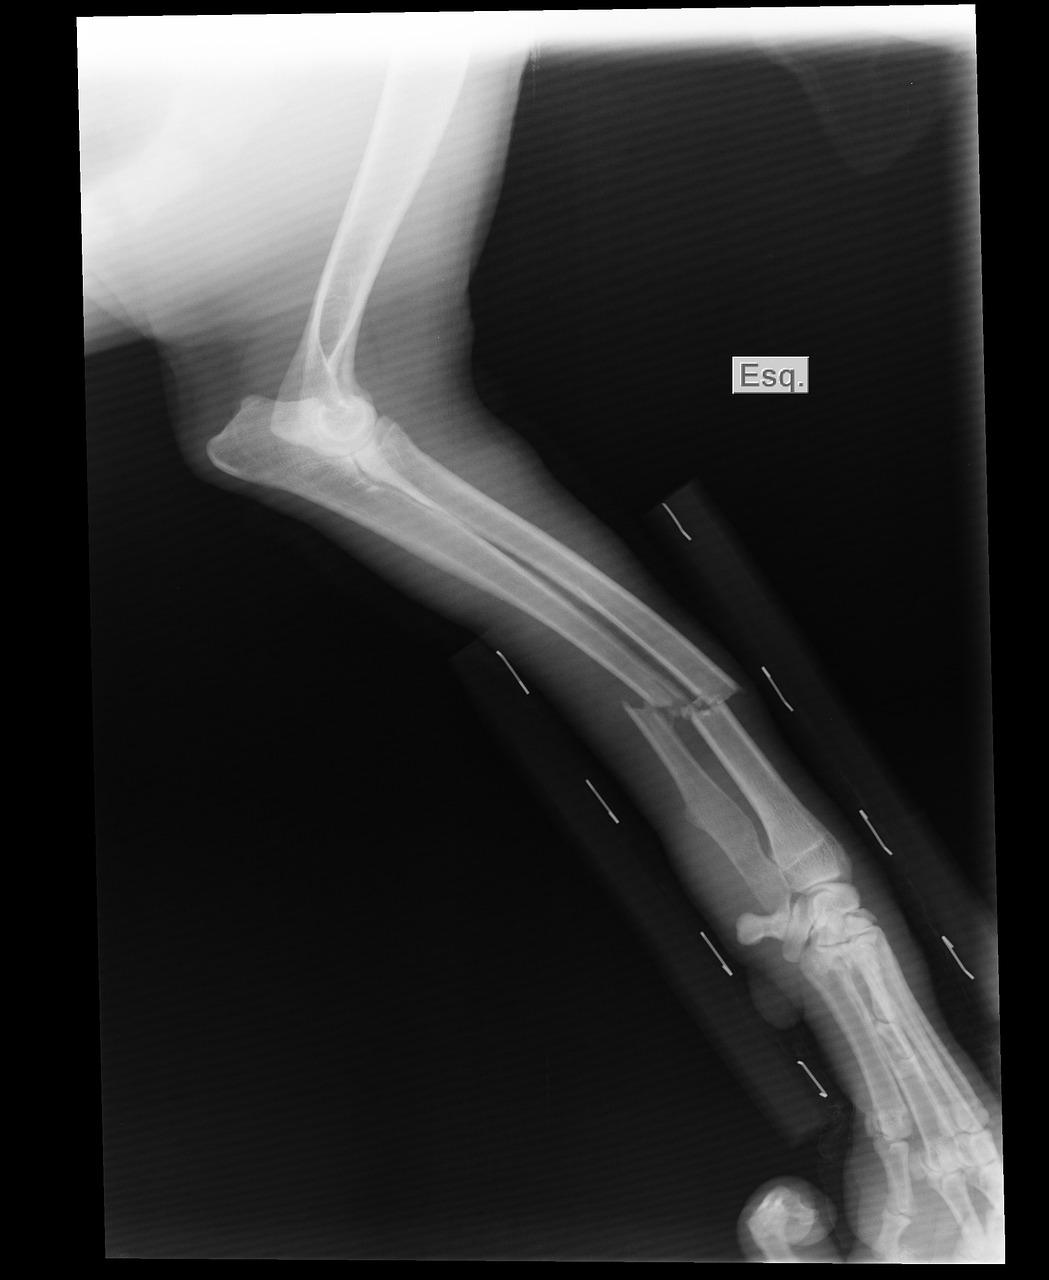

Sprawdź wszystkie najważniejsze informacje o badaniu RTG?